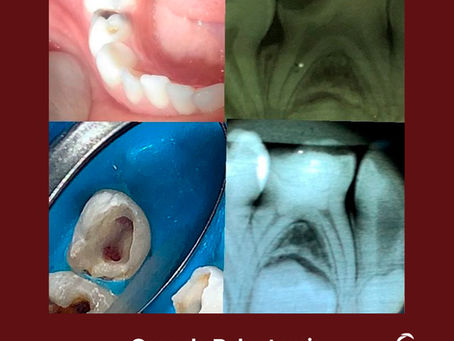

Casos clínicos

Explore nossos casos clínicos sobre o uso de cimento biocerâmico Cimmo: aplicações reais, abordagens práticas e resultados transformadores para inspirar e aprimorar sua prática odontológica.